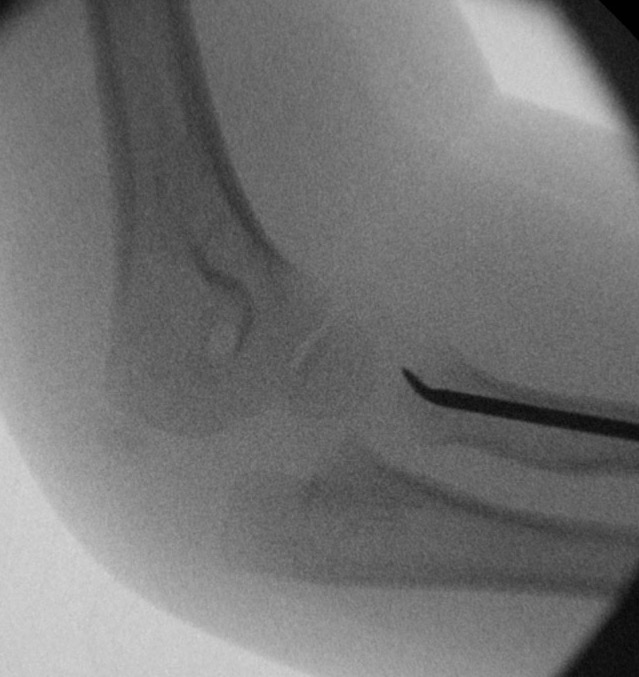

Xray

Displaced and angulated radial neck fracture